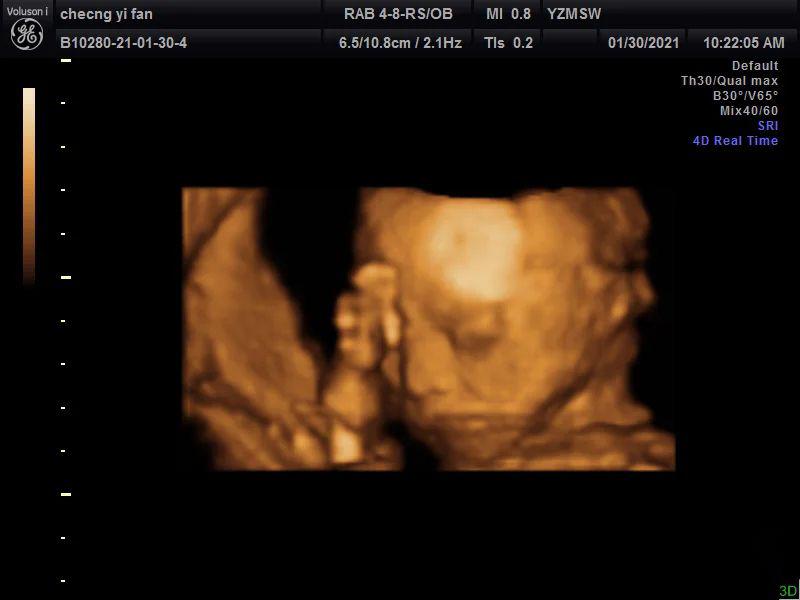

第二天四维是孕23周+4天,约了一个私立医院,主要是可以保存宝宝的照片和视频,于是就去了,这次是早上,宝宝非常配合(图三到图七)!脸和脚,小拳头,都拍的特别清楚,医生说宝宝很好看,尖尖的下巴,鼻梁好好的,眼睛也很大,到最后手放在脸上,还对我比了个✌️嘻嘻嘻,希望四维照片和宝宝出生照像一些~